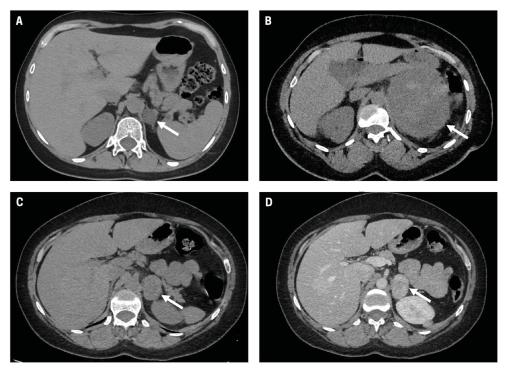

A. TDM en contraste spontané montrant un adénome surrénalien gauche (flèche) : lésion à contours réguliers, homogène, densité spontanée < 10 UH.

B. TDM en contraste spontané montrant un cortisosurrénalome gauche (flèche) : lésion à contours irréguliers, hétérogène, de grande taille, avec effet de masse sur les organes adjacents.